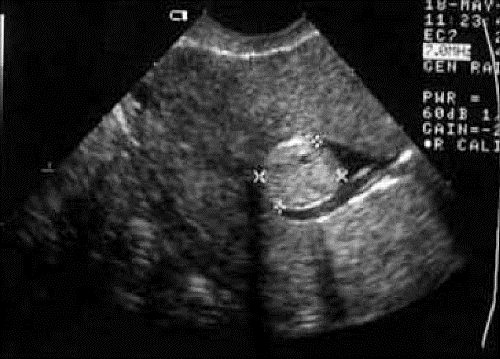

Беременность- 1 триместр ( только до 10 недель)Девочки не сочтите за умалишенную, просто все впервые и так переживаю сильно, что ничего не могу с собой поделать:((((. По месячным сегодня ровно 5 неделе ( последние 21 сентября). Пошла уже на второе узи, первое мне сделали, конда хгч был 287, зачем не знаю, естественно ничего не было, врач в больнице напусла всем чем можно. 2 дня назад хгч уже был 2213 и я сегодня пошла на узи. Вот сразу мне узист не понравилась, очень грубая и нервная. Нашла ПЯ в матке, размером 8.6 мм ( в заключении написано, что соответствует 3м неделям) и кисту желтого тела 2×2 см, на прошлом узи 5 дней назад ее не было. Я обрадовалась и успокоилаь. Пришла домой и потом до меня дошло, что у меня же есть интрамуральная миома как раз 8-10 мм, про которую она мне ничего не сказала. Вот теперь сижу и не могу уняться: могли ли она перепутать ПЯ с миомой, или это я уже с ума схожу?:(((( к слову, на первом узи в другом месте, про миому тоже ничего не говорили, пока я не спросила. Нормальный ли размер ПЯ для 3 недель и что желать с кистой? К Г только завтра, но я до завтра поседею тут:(((

Миома выглядит иначе.